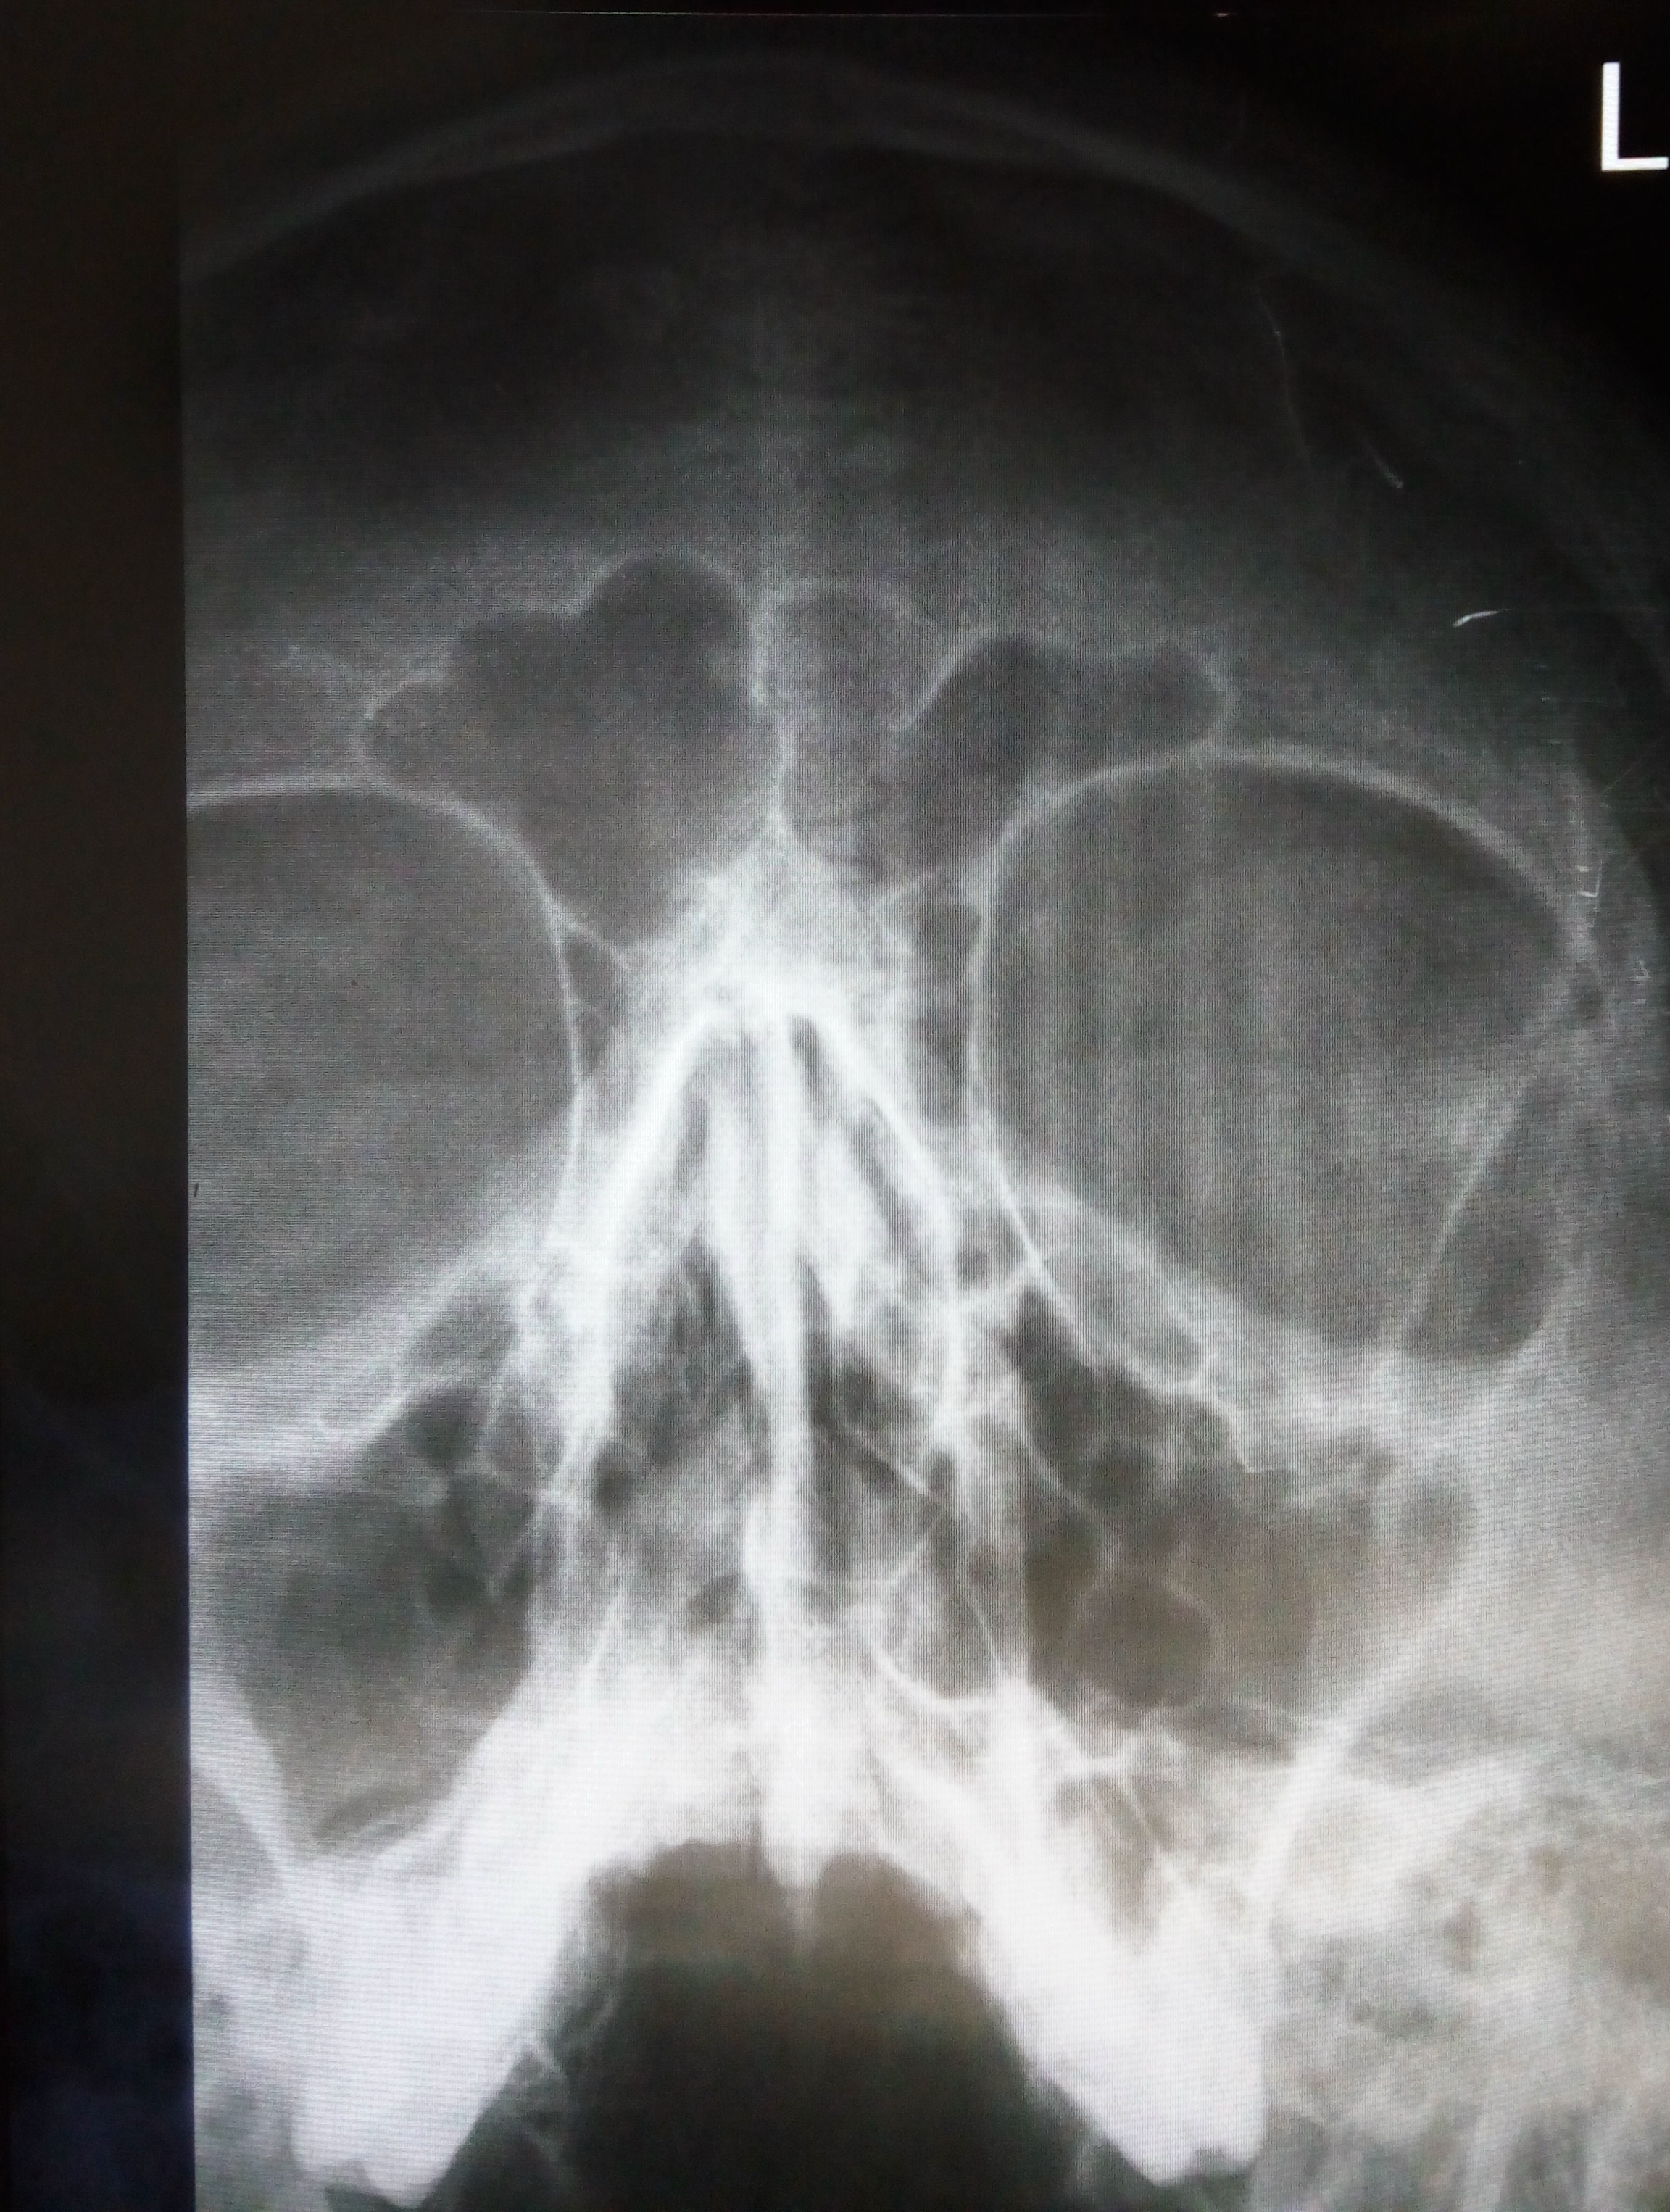

Остеома решетчатого лабиринта

Остеома лобной пазухи